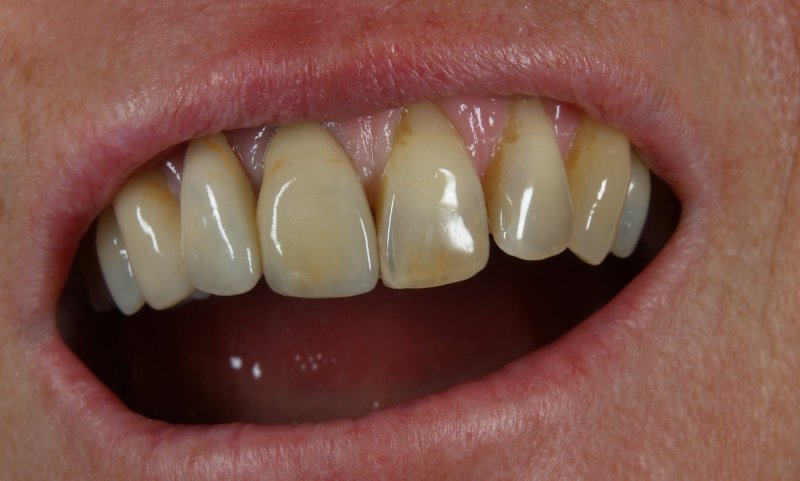

Vom Langzeitprovisorium zur TEK 1 Arbeit